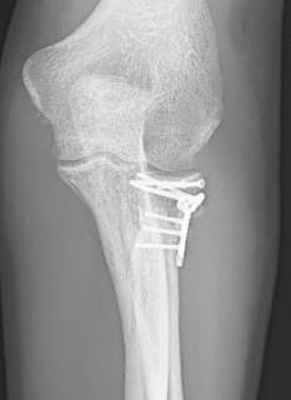

2. Реконструкция головки лучевой кости и пластинами с угловой стабильностью

Лечение пациента с многооскольчатым переломом (Тип 3) после падения с горного велосипеда: Комбинированный остеосинтез с применением пластин с угловой стабильностью. Рентген показывает состояние сустава после заживления. © Gelenk Klinik

Даже сложные переломы с несколькими отломками и вывихами можно вылечить при помощи остеосинтеза. Для этого в Геленк Клинике используются специальные пластины с угловой стабильностью, которые надежно фиксируют отдельные фрагменты сустава